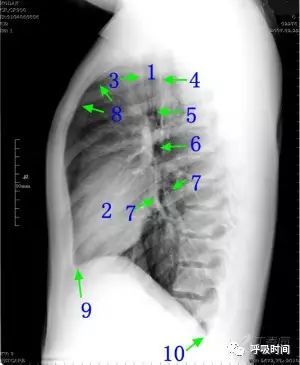

图片

图 1 为胸部正侧位片

双肺(血管)纹理清晰(至胸膜下 3 cm / 限于肺野中内带);肺门结构不大、清晰。心影大小形态无异常,纵隔无偏移。双侧肋膈角锐利,胸廓对称